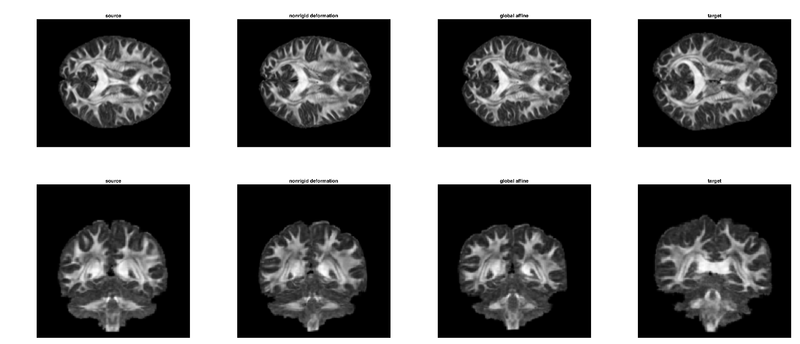

Nonrigid registration of two HCP 90-direction DWI volumes. Shown here from two slice views are the Generalised FA. From the left: (1) interpolated source, (2) nonrigid registration (compare with source), (3) affine registration. (4) interpolated target.